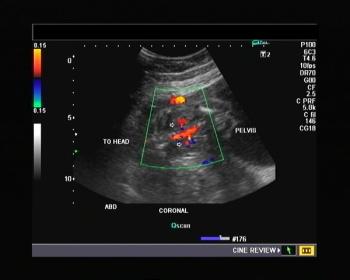

Name the vessels shown in this color Doppler image of a fetal abdomen in 22 week-old fetus. Is anything abnormal?